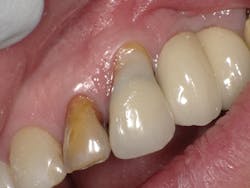

Case Three is a challenging crown repair on a medically compromised patient. The preoperative image shows decay at the buccal margin of an anterior abutment to a bridge (figure 11). Following excavation with the Lite Touch laser (figure 12), we decided to use Futurabond U in a self-etch technique followed by layering Admira Fusion in two increments. The first increment was an opaque layer, using shade OA2 to attempt to block out the gray margin of the porcelain-fused-to-metal crown (figure 13). After light-curing that layer, we applied shade A1 and light-cured and polished the restoration, achieving a highly esthetic result given the difficulty of the situation (figure 14).

Figure 12